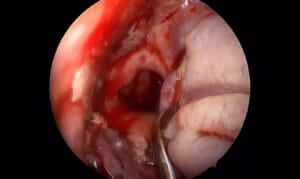

Dehiscencia bilateral de conducto semicircular superior

El Dr. Casado realiza un abordaje de fosa media endoscópico para reparar una dehiscencia bilateral de conducto semicircular superior.